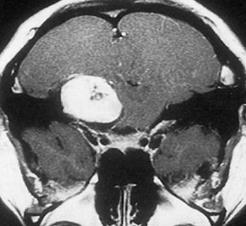

Vannak olyan neurológiai állapotok, amelyek okozhatnak n. trigeminus károsodást, ide tartoznak a sclerois multiplex, és a kevert kötőszöveti betegséggel járó neuropathia. Hasonló eredménye lehet az intracranialis térszükítő folyamatnak (pl. acusticus neuroma, 18.2. ábra).